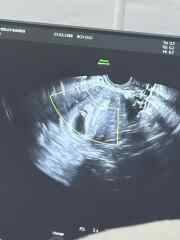

Just for fun really as I know it’s 50/50 but anybody any good at guessing this haha? Transvaginal scan. 7 weeks 5 days but measuring 6 weeks 6 days at the time of the scan 🤍 thank you xx